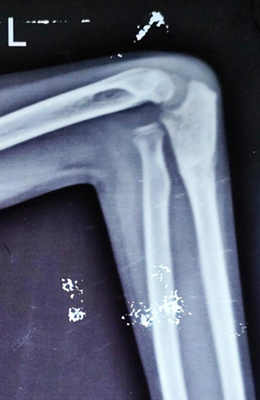

Failed Primary Fixation of Monteggia Fractures – A Case Series

Sujata Aiyer , Yogesh Mudholkar , Ravi Trivedi , Apoorv Gota , Aniket Wankhede , Saiprasad Madavi

………………………………p.274-279